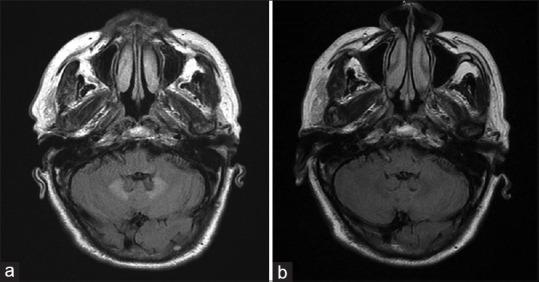

Metronidazole-induced encephalopathy (MIE) is a rare but serious complication caused by metronidazole, a widely used antianaerobic drug. Previous studies prescribed MIE including dysarthria, cerebellar ataxia, and confusion after long-term use of metronidazole. Malignancy has been proposed one of the predisposing conditions for MIE. However, the occurrence of MIE in cancer patients remains unknown.

Findings in 793 cancer patients who underwent metronidazole therapy for anaerobic infection revealed two cases of MIE. One had renal cell carcinoma and the other had bladder urothelial carcinoma. Both of their initial presentation were cerebellar dysfunction. The occurrence of MIE was 8.6% for cases who received >30 g of cumulative dose. Hypertension was the most common comorbidity, followed by chronic renal disease and diabetes mellitus.

In cancer patients, MIE should be monitored in those with genitourinary cancer, especially with renal dysfunction. Longer duration with more cumulative dose also has a greater risk of MIE. Early consideration of MIE with prompt cessation of metronidazole may result in better outcome.